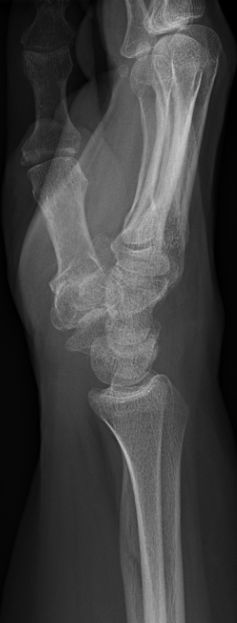

Exempel på luxation av pisiforme, har också fraktur i skafoideum. Utreddes även med DT, pisiforme exciderades av handkirurg.